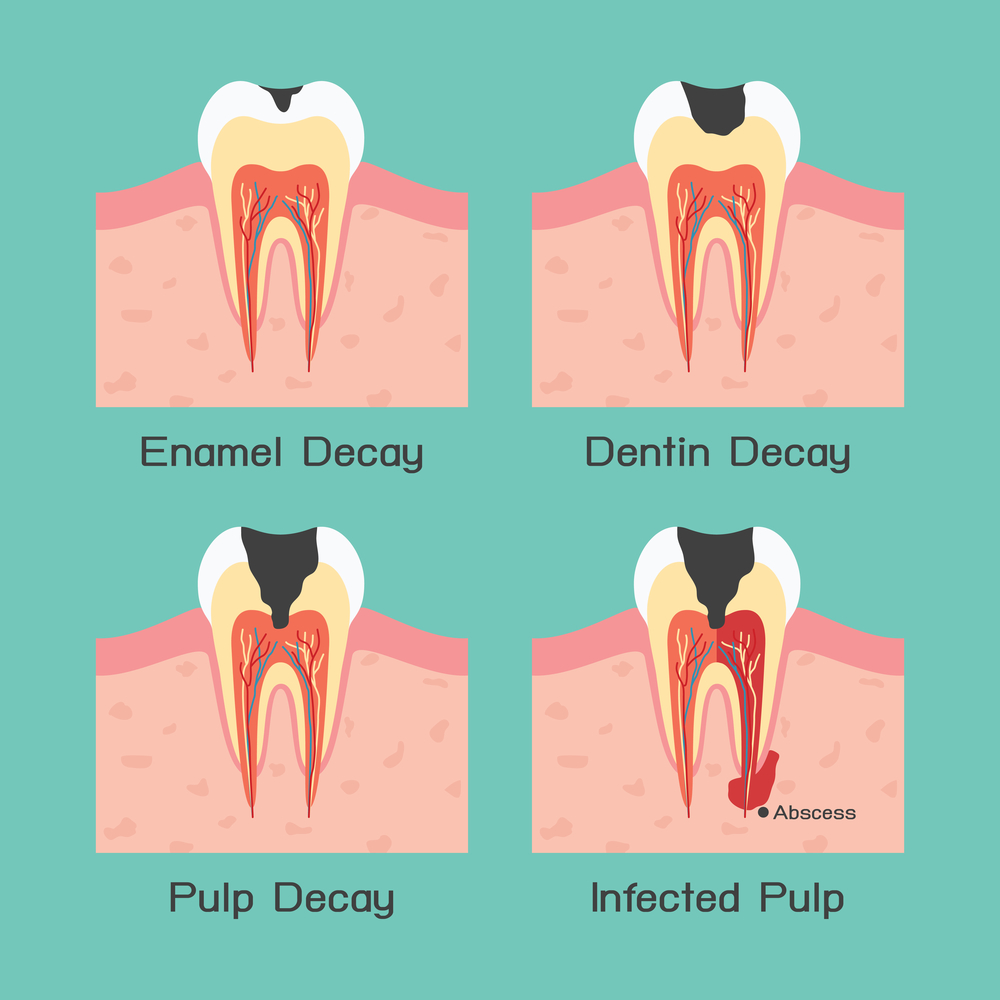

The 5 Stages Of Tooth Decay | News | Dentagama

tooth dental decay abscess stages caries dentagama phoenix pain pulp infection teeth bone like spread look mouth periodontal severe enamel

Stages Of Dental Decay And Periodontal Disease | High Dosage

dental decay disease caries stages teeth

Tooth dental decay abscess stages caries dentagama phoenix pain pulp infection teeth bone like spread look mouth periodontal severe enamel. Symptoms and treatments of dental caries. Stages of dental decay and periodontal disease